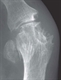

Usually, radiographs do not show characteristic features of gout until late in the disease (see figure 4, p13). However, joint ultrasound readily demonstrates characteristic features (microtophi in synovium and periarticular sites, crystal deposits in superficial articular cartilage producing a parallel double contour sign aligned with subchondral bone, and bone erosions) at first presentation in multiple peripheral sites, not just the presenting symptomatic joint.24 Dual energy computed tomography (DECT) can also identify urate crystal deposits but is less widely available than ultrasonography.

It is particularly useful in diagnosing uncommon axial gout.